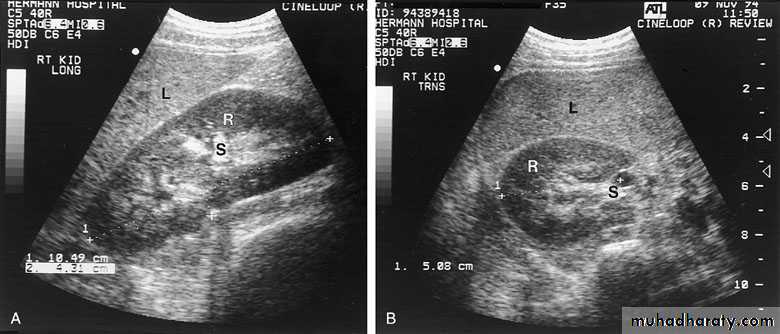

ULTRASONOGRAPHY (U/S )Structural study to differentiate cystic or solid masses, hydronephrosis, renal size, renal cortical thickness, and stones.

A calculus in the kidney casts an acoustic shadow